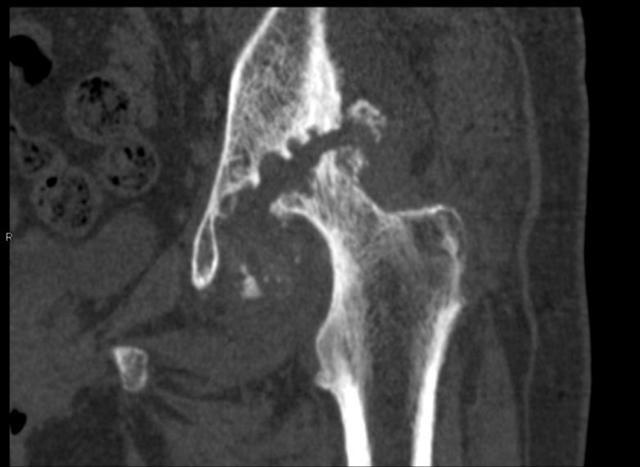

骨頭的空隙處是已經(jīng)消失缺損的髖臼。

70歲的彭阿姨家住漢陽,一周前她因髖部疼痛劇烈,無法行走,被子女送到武漢市第一醫(yī)院骨科住院治療。管床醫(yī)生張麟檢查發(fā)現(xiàn),彭阿姨的左腿比右腿短了3厘米,片子上左側(cè)股骨頭已經(jīng)消失看不見了。

剛開始,她感覺腿舒服了不少,一段時(shí)間后疼痛反復(fù)且更加嚴(yán)重,以為是藥量不夠,就加量服用。沒想到現(xiàn)在痛得連路都走不了。彭阿姨最終確診為左側(cè)股骨頭無菌性壞死,髖臼缺損,接受左側(cè)髖關(guān)節(jié)置換術(shù)后,15日康復(fù)出院。